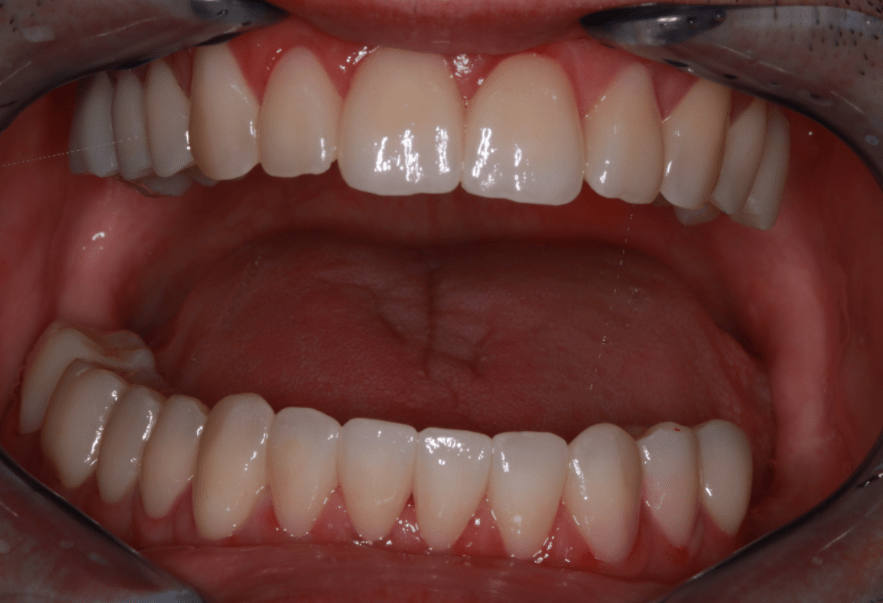

Klinikai és radiológiai vizsgálatok alapján megállapítottam, hogy a túlterhelés (parafunkciók) jelei látszódnak a fogain is: abfrakciók – nyaki kopások és attríciók –, rágófelszíni kopások is kifejezettek voltak. Harapása igen bizonytalan tartományban mozgott, nem volt egy stabil helyzet, amelybe határozottan össze tudott volna zárni (csak kereste a megfelelő pozíciót.) TMI-vizsgálat során reciprok crepitációt (kattanás nyitáskor-záráskor is), myofascialis eltéréseket (hypertrófiás musculus masseter – túlterhelt rágóizom) és beszűkült mozgáspályákat találtam. Emellett sajnos a nem megfelelő szájhigiénés szokások miatt a fognyakak „sérült” részein szuvasodások is megjelentek, illetve a bal alsó hatos és a jobb felső hetes fog már oly mértékben destruálódott, hogy el kellett távolítani őket.

A nagy kiterjedésű szuvasodások ellátására, továbbá a harapási forma és ezzel együtt az ízületi panaszok megszüntetésére full kontúr cirkón pótlást terveztem, melyet individuálisan a rendelőnk ARCUSdigma készülékének segítségével készítettem el.

Miután a pácienssel megbizonyosodtunk a pótlás funkcionalitásának sikerességéről, készre kértük a fogtechnikai laborból azt a cirkóniumpótlást, amely a kisebb korrekciókon átesett ideiglenes pótlás tökéletesen pontos mása lett.

A páciens az elért eredménnyel mind funkcionálisan, mind esztétikailag azóta is maximálisan elégedett.